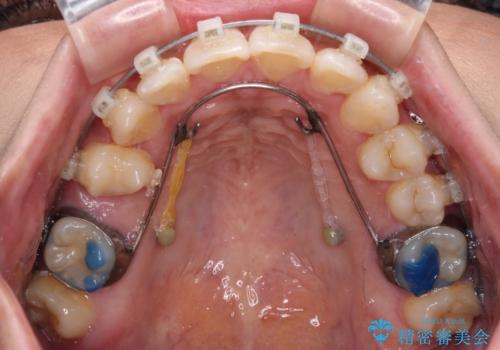

- クリアブラケット

- 2年1ヶ月

上顎小臼歯を抜歯するかどうか悩みましたが、八重歯の後方に失活歯があること、治療前に上顎正中が概ね人中に合っていることから、右上第二小臼歯を抜歯することとしました。

片側での抜歯であると、正中が抜歯した方向にずれていくため、左上の奥歯を遠心移動させる目的でアンカースクリューと補助装置を併用した上で、ワイヤー装置にて矯正治療を行うこととしました。

上顎の正中位置をほぼ保った状態で、綺麗に仕上げることができました。